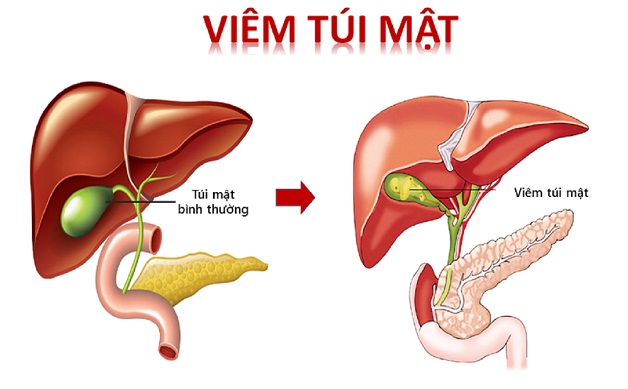

Vì sao cần phòng ngừa bệnh sỏi mật?

Không phải ai mắc sỏi mật cũng có triệu chứng rõ ràng, nhưng một khi sỏi gây tắc nghẽn đường mật hoặc viêm túi mật cấp, tình trạng có thể trở nên nguy hiểm. Nhiều bệnh nhân buộc phải sử dụng biện pháp can thiệp như nội soi, thậm chí phẫu thuật cắt túi mật để tránh biến chứng.

Hiểu đúng về sỏi mật và sỏi thận – tránh nhầm lẫn

Nhiều bệnh nhân thường nhầm giữa triệu chứng sỏi mật và sỏi thận do cùng gây đau vùng bụng. Tuy nhiên, đây là hai bệnh lý khác nhau, thuộc hai hệ cơ quan riêng biệt. Một số người có thể mắc cả hai bệnh cùng lúc và cần áp dụng biện pháp điều trị phù hợp cho từng vị trí.

Ví dụ, nếu phát hiện sỏi đường tiết niệu, bác sĩ có thể chỉ định tán sỏi thận song song với việc theo dõi sỏi mật. Vì vậy, việc phân biệt rõ giúp bác sĩ đưa ra phác đồ chính xác và tránh điều trị sai hướng.

Khi nào cần can thiệp điều trị?

Dù hướng chính vẫn là phòng ngừa bệnh sỏi mật, một số trường hợp buộc phải điều trị vì sỏi gây biến chứng.

Ví dụ:

- Sỏi lớn gây tắc nghẽn liên tục

- Viêm túi mật tái phát

- Nguy cơ nhiễm trùng đường mật

- Đau kéo dài ảnh hưởng sinh hoạt

Khi đó, bác sĩ có thể chỉ định nội soi lấy sỏi hoặc can thiệp ngoại khoa. Trong trường hợp túi mật bị tổn thương nặng, phương pháp phẫu thuật cắt túi mật thường mang lại hiệu quả triệt để.